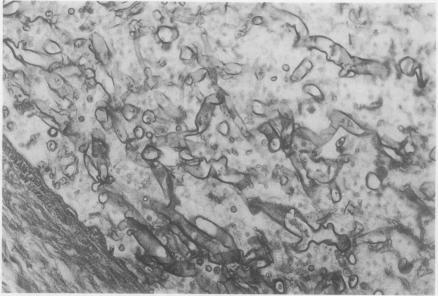

Endobronchial zygomycosis.

Thorax. 1987 Jul;42(7):553-4. doi: 10.1136/thx.42.7.553.